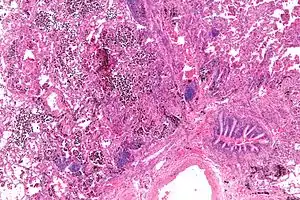

| Micrograph showing a pulmonary haemorrhage. H&E stain. | |